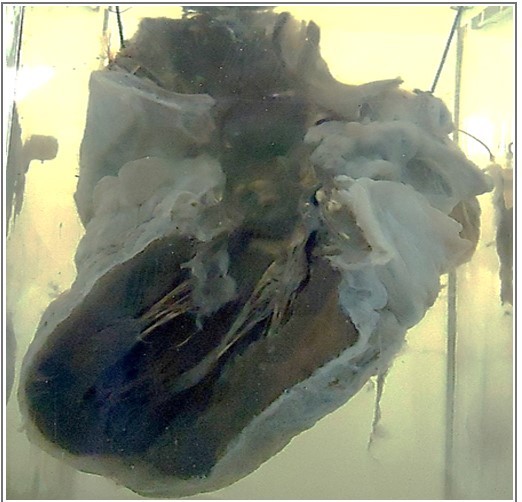

Q

what is this

A

heart with open left side

13

HEART is reduced in _________ with _______

1. The myocardium is _________ in color

2. PERICARDIAL FAT is replaced by ___________.

3. AORTA shows ____________.

size, tortuous coronaries

dark brown

edematous tissue

yellow atherosclerotic patches

14

diagnosis

brown atrophy of the heart

brown atrophy of pericardial fat

aortic atherosclerosis